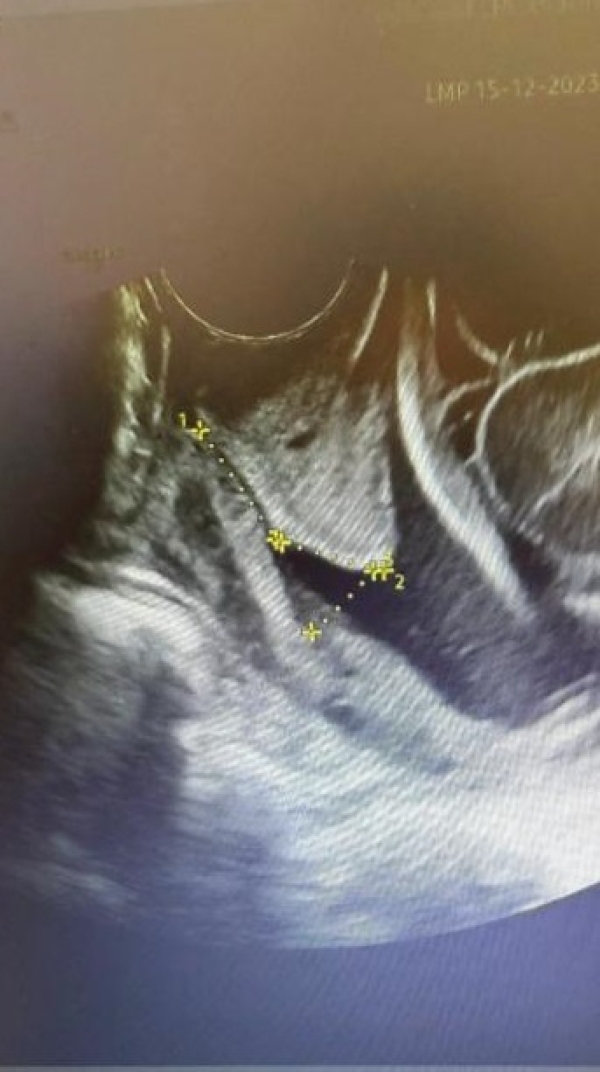

Servikal Yetmezlik Nedir?

Serviks (rahim ağzı), uterusun (rahmin) vajinaya açılan alt kısmıdır. Servikal yetmezlik, gebeliğin 14-28. haftaları arasında ağrı olmadan serviksin açılması ve bebeğin doğması durumudur. Kesin ...